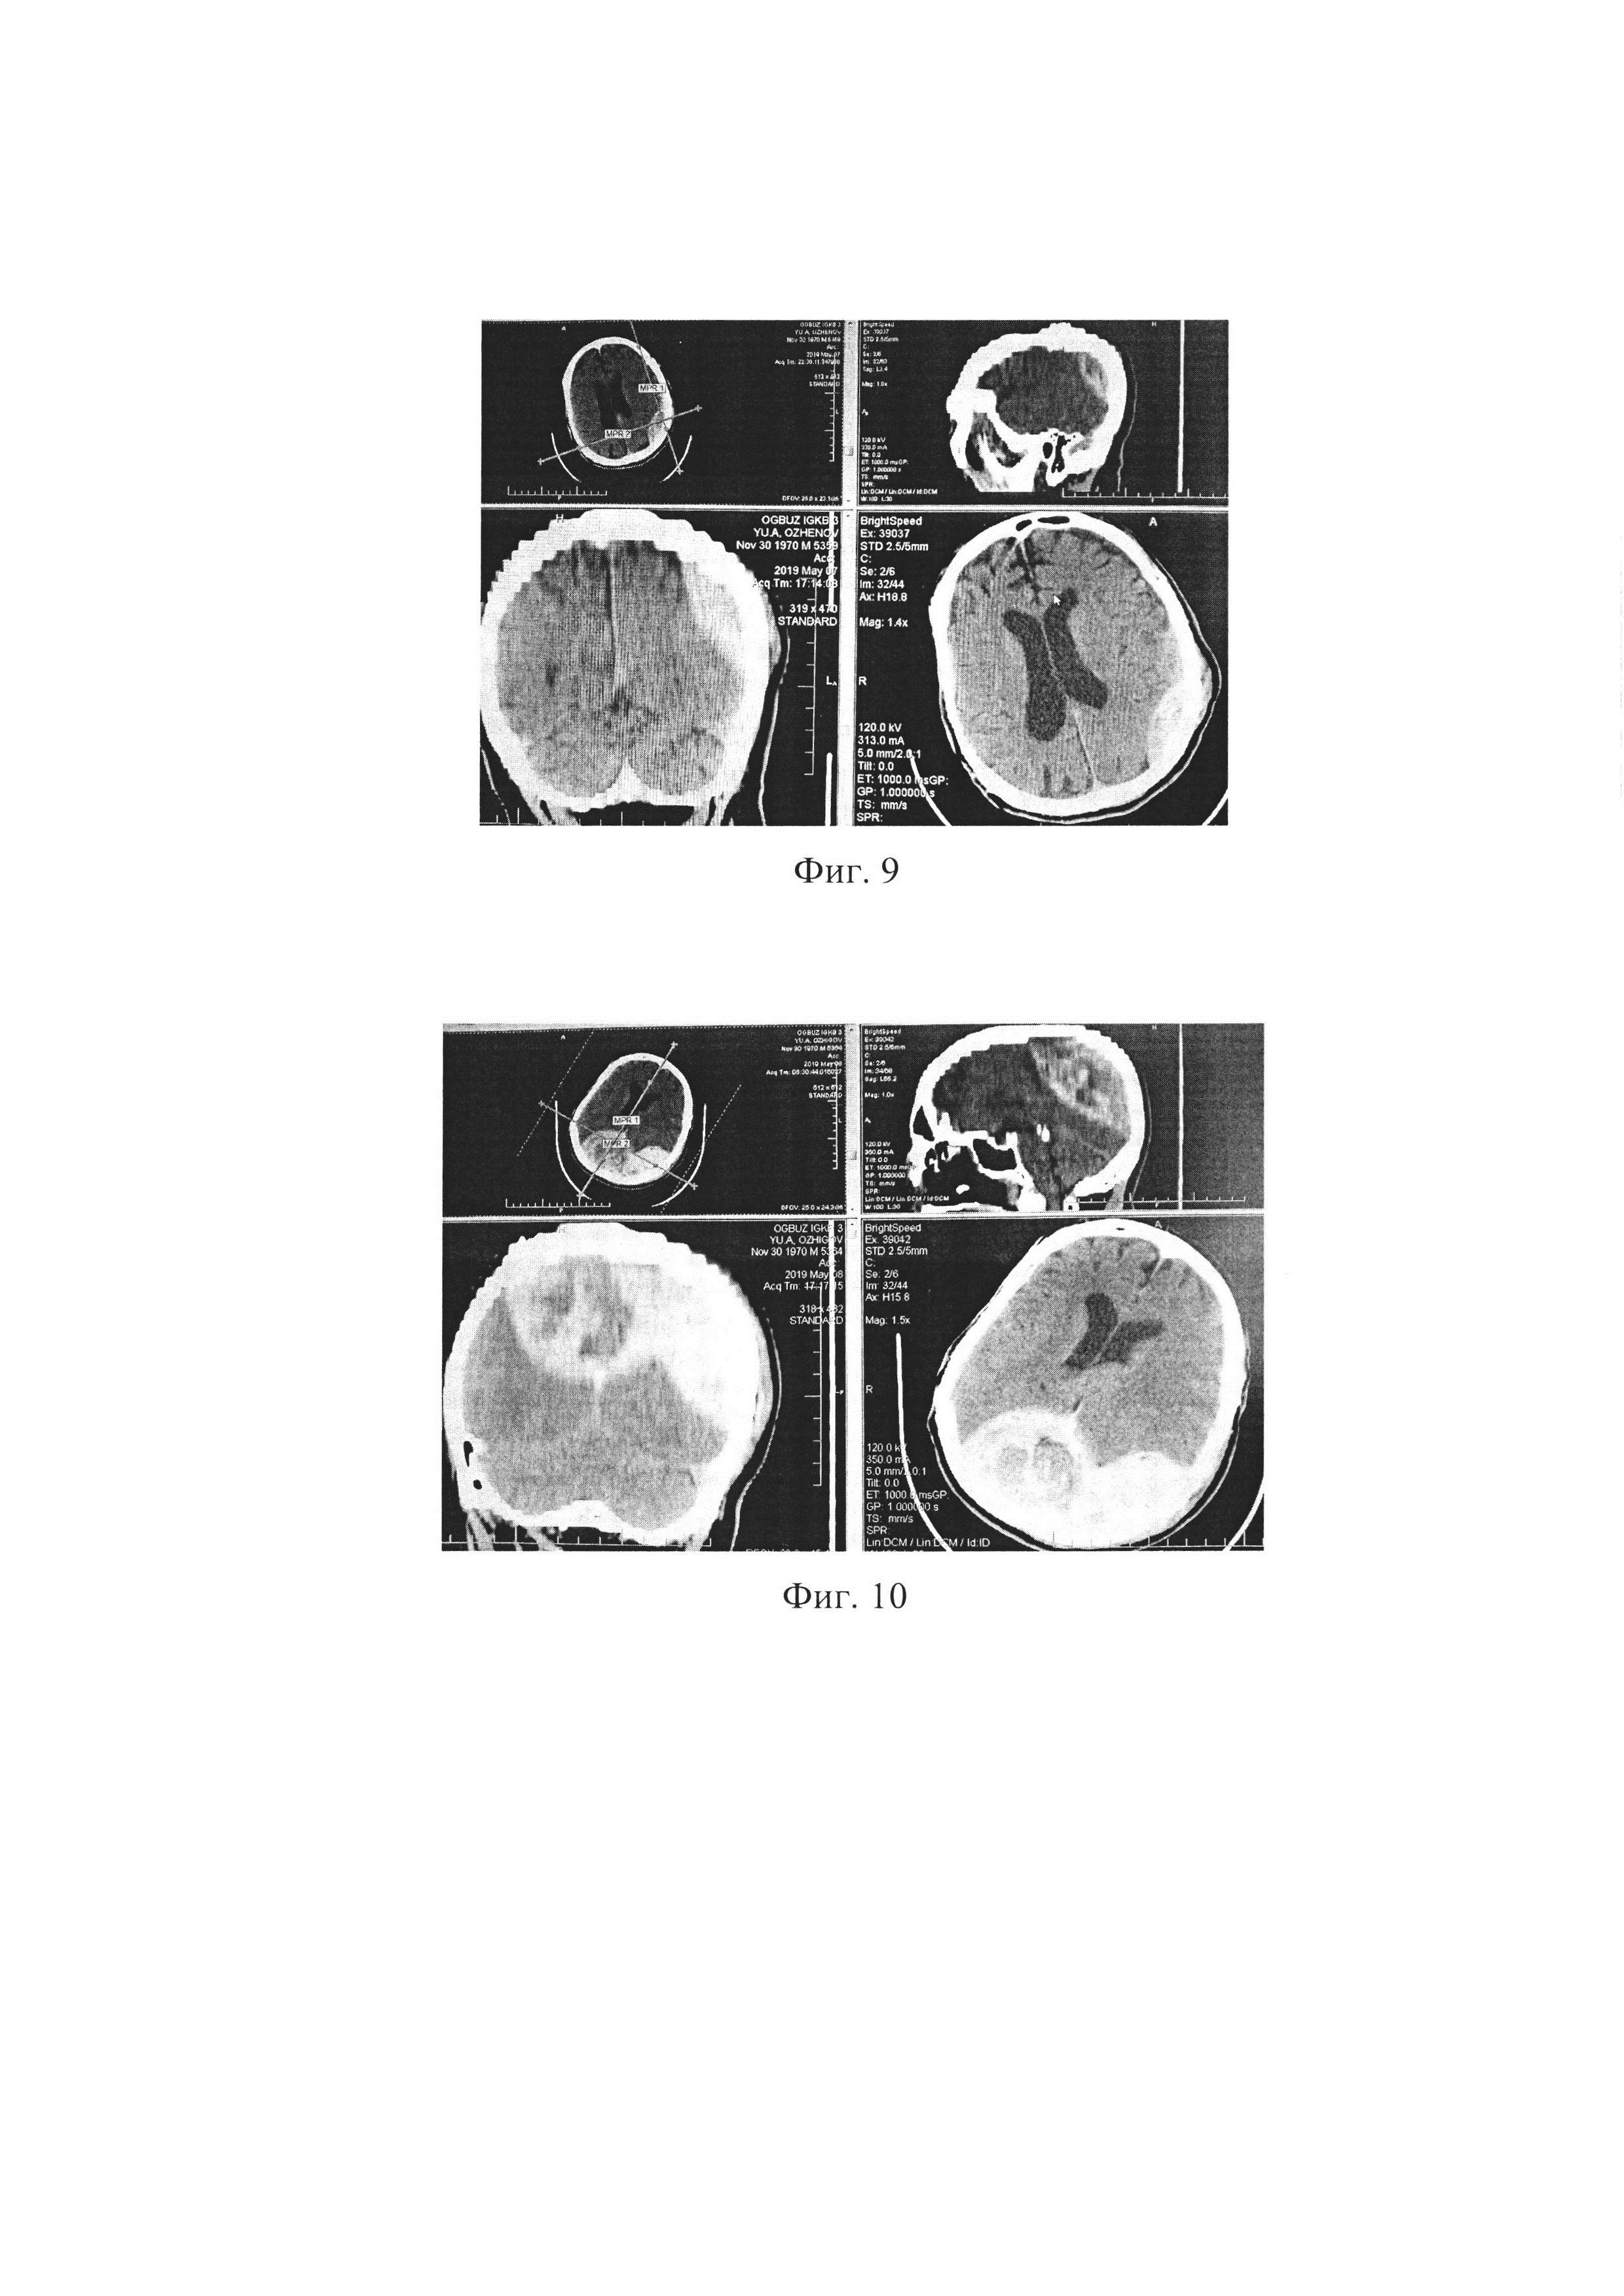

При поступлении выполнена МСКТ головного мозга. Заключение: внутримозговая гематома правой лобно-теменной области; субдуральная гематома левой лобно-теменно-височной области; контузионные очаги левой теменной области I вида; линейный перелом лобной и левой теменной костей; латеральная дислокация срединных структур (фиг. 12).

[88]

Диагноз клинический: ЗЧМТ, ушиб головного мозга тяжелой степени со сдавлением ОСГ слева, ОВМГ в лобной доле справа; субарахноидальное кровоизлияние, внутрижелудочковое кровоизлияние; линейный перелом костей свода черепа; дислокационный синдром.

[89]

При анализе МСКТ исследования установлен объем ОСГ слева 60 мл, объем ОВМГ справа - 40 мл; РГХЯ=15 мм; ДОЗН справа равен 5 мм, ДОЗН слева равен 5 мм, ДОЗНср.=5+5/2=5 мм;

[90]

ОВИ=5×100/15=33,3% (т.е. меньше 53,9%) - риск развития гипотензивной реакции головного мозга по типу коллапса. Пациенту по жизненным показаниям выполнена КПТ слева в связи с широким распространением гематомы, удалена ОСГ, а также ТЧ справа, дренирование ОВМГ. Во время операции отмечена «гипотензивная» реакция мозга в виде его «западения». На 2 сутки после операции по результатам МСКТ у пациента Ш. подтверждена «гипотензивная» реакция мозга по типу коллапса с образованием пневмоцефалии (фиг. 13).

[91]

В послеоперационном периоде пациент с положительной динамикой, на 11 сутки переведен из ОАиР в отделение нейрохирурги с регрессом неврологической симптоматики; переведен в неврологический стационар на реабилитационное лечение на 33 сутки после госпитализации.